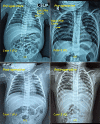

Figure 1

Figure 1. CXR pre-operative: (a) P1 showing CPAM cavity in left upper lobe of lung, (b) P2 showing CPAM cavity in right upper lobe of lung, (c) & (d) CXR postoperative

CXR - Chest X-ray; CPAM - Congenital pulmonary airway malformation; P - Patient Image Credit: Dr. Vishal V. Bhende